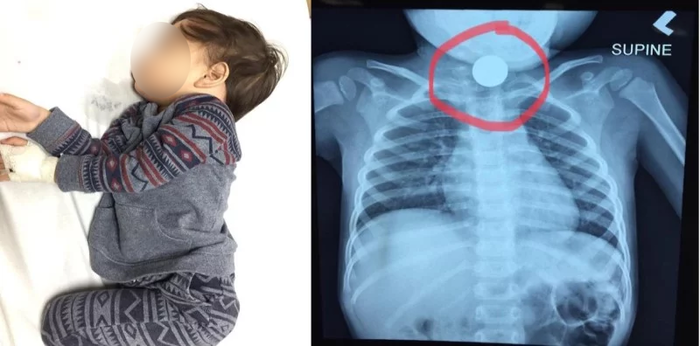

Batang nakalunok ng barya

Isang bata sa Malaysia ang nakalunok ng barya. Ngunit bago matanggal ito at tuluyang mailigtas ang bata ay dumaan pa ang 24 oras. Ito ay dahil sa kakulangan ng maayos na medikal na pasilidad sa kanilang lugar.

Kwento ng ina ng bata sa kaniyang Facebook account, bandang alas-11 ng gabi ng mapansin niya at kaniyang asawa na matamlay at hirap huminga ang kanilang anak na si Reza. Ito pala ay nakalunok ng isang bagay na nakabara sa lalamunan niya.

Sinubukan nilang tanggalin ang nakabara sa lalamunan ng anak sa pamamagitan ng pagpapaubo dito. Pero hindi parin ito naialis. Kaya naman nag-iiyak na ang kanilang anak at nagsimula naring isuka ang mga gatas na nadede niya.